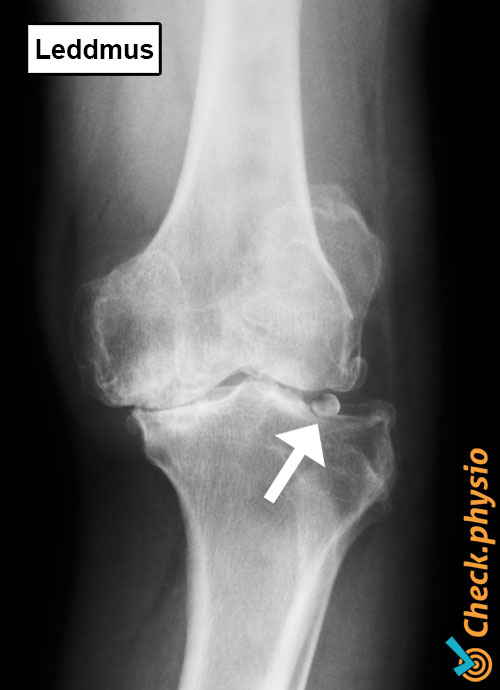

Corpus liberum Leddmus / løst fragment i leddet

Diagnosen stilles som regel basert på pasientens sykehistorie. Ved klinisk undersøkelse av leddet forsøker legen eller fysioterapeuten å fremkalle symptomene, noe som ikke alltid er mulig. Tilleggsundersøkelser er nødvendig for å gjøre corpus liberum synlig. På en røntgen eller MR er corpus liberum ofte lett å oppdage.